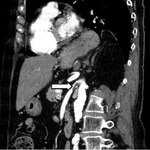

Abscesso hepático: tomografia computadorizada (TC) (vista coronal) mostrando abscesso hepático em um homem de 46 anos de idade que apresentava febre, fadiga e tosse

Do acervo de imagens radiológicas do Massachusetts General Hospital